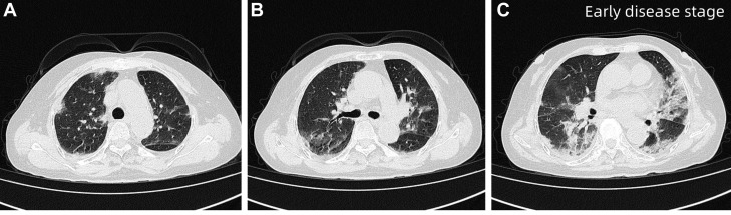

入院时行高分辨率CT(HRCT),显示双肺弥漫性斑片状致密影,边缘模糊,以双下肺为主,局部可见空气支气管征,提示急性弥漫性肺实质受累。

图1 患者入院时HRCT,双肺弥漫性斑片状致密影,边缘模糊,双肺下叶为主要受累区域,局部可见空气支气管征

住院第13天,患者病情短暂稳定后,在高流量氧疗(吸氧浓度65%,流量50L/min)支持下安全复查HRCT,显示双肺炎症明显加重,呈广泛磨玻璃影伴部分实变,肺间质受累加重,同时可见双侧胸腔积液及局灶性肺不张,较入院影像明显进展。

图2 患者住院第13天HRCT 图像,显示双肺弥漫性磨玻璃影伴部分实变(红色箭头),以双肺下叶为主,可见局部空气支气管征及双侧胸腔积液(右侧更为明显)

经过超过1个月的治疗后,患者呼吸困难较前改善,但未完全缓解。复查HRCT显示双肺弥漫性斑片状磨玻璃影伴小叶间隔增厚,呈“铺路石样”改变,并见局部空气支气管征。鉴于治疗改善不足,患者在行鼻导管吸氧(3L/min)的同时进一步行支气管镜检查检查,发现BALF呈乳白色,PAS染色阳性,提示肺泡内蛋白样物质沉积。

图3 患者治疗1个多月后HRCT,显示双肺弥漫性斑片状磨玻璃影伴小叶间隔增厚,呈铺路石样改变(黄色箭头)

治疗4个月后对患者进行随访,HRCT显示双肺纹理略增粗,弥漫性磨玻璃影较前明显减轻。